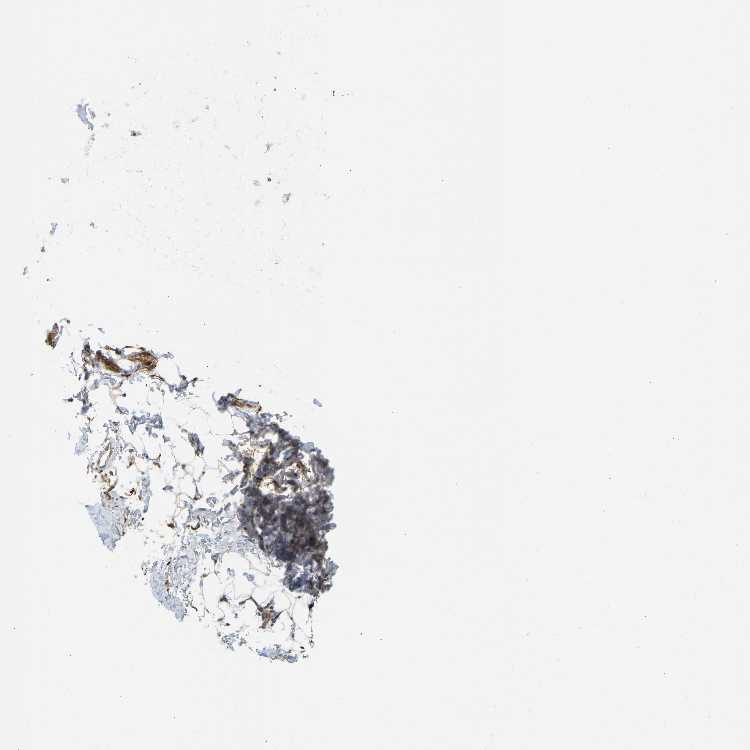

ADIPOSE TISSUE - Antibody stainingi

Antibody staining in the annotated cell types in the current human tissue is reported as not detected, low, medium, or high, based on conventional immunohistochemistry profiling in selected tissues. This score is based on the combination of the staining intensity and fraction of stained cells.

Each image is clickable and will lead to virtual microscopy that enables deeper exploration of all samples and also displays staining intensity scores, fraction scores and subcellular localization as well as patient and tissue information for each sample.

Antibody HPA019053Antibody HPA019061

Adipocytes HighLow